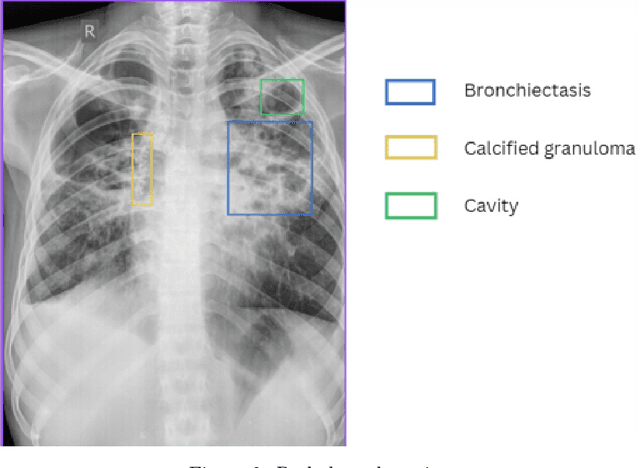

Abstract:Background This study proposes a Vision-Language Model (VLM) leveraging the SIGLIP encoder and Gemma-3b transformer decoder to enhance automated chronic tuberculosis (TB) screening. By integrating chest X-ray images with clinical data, the model addresses the challenges of manual interpretation, improving diagnostic consistency and accessibility, particularly in resource-constrained settings. Methods The VLM architecture combines a Vision Transformer (ViT) for visual encoding and a transformer-based text encoder to process clinical context, such as patient histories and treatment records. Cross-modal attention mechanisms align radiographic features with textual information, while the Gemma-3b decoder generates comprehensive diagnostic reports. The model was pre-trained on 5 million paired medical images and texts and fine-tuned using 100,000 chronic TB-specific chest X-rays. Results The model demonstrated high precision (94 percent) and recall (94 percent) for detecting key chronic TB pathologies, including fibrosis, calcified granulomas, and bronchiectasis. Area Under the Curve (AUC) scores exceeded 0.93, and Intersection over Union (IoU) values were above 0.91, validating its effectiveness in detecting and localizing TB-related abnormalities. Conclusion The VLM offers a robust and scalable solution for automated chronic TB diagnosis, integrating radiographic and clinical data to deliver actionable and context-aware insights. Future work will address subtle pathologies and dataset biases to enhance the model's generalizability, ensuring equitable performance across diverse populations and healthcare settings.